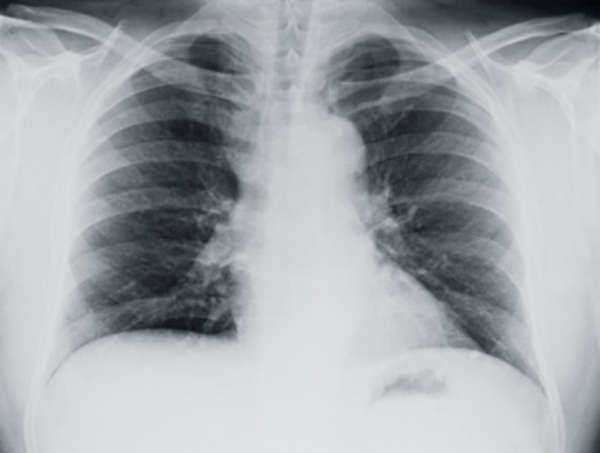

3. Mesotelioma generalmente se detecta mediante el uso de una radiografía de tórax o mediante una biopsia. El tumor se asocia a menudo con mesotelioma veces puede ser evidente a través de una radiografía, aunque no es raro que una biopsia es necesaria para determinar formalmente la presencia de mesotelioma.